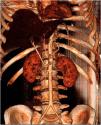

We report the case of a 37-year-old male, with no significant past medical history, who, five days after receiving the Janssen Covid-19 vaccine, began experiencing language impairment, disorientation, and psychomotor restlessness. A brain CT scan revealed the presence of left middle cerebral artery ischemia (Fig. 1), as well as a platelet count of 25 000/mm3, which raised suspicion of vaccine-induced thrombotic thrombocytopenia (VITT). This suspicion was later confirmed with positive antibodies against platelet factor 4. Despite treatment with fondaparinux, corticosteroids, and immunoglobulins, the patient's disease progression was poor, with development of abdominal distension with peritonitis and rapid respiratory deterioration that eventually requiring mechanical ventilation. The abdominal CT scan performed at six hours revealed the presence of enterocolic, pancreatic, and gastric ischemia with extensive thrombosis of the portomesenteric axis (Fig. 2 and Fig. 3). Ultimately, the patient passed away